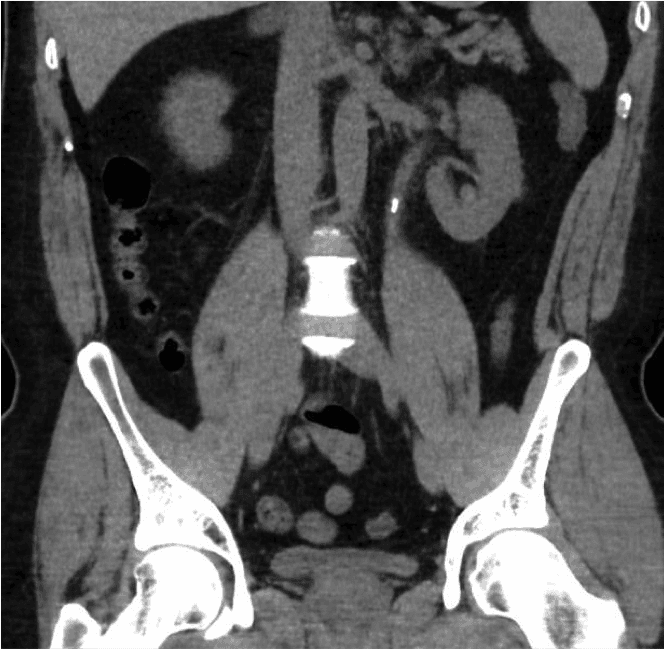

गुर्दे की पथरी की बीमारी आधुनिक युग की सबसे आम बीमारियों में से एक है। भौगोलिक स्थानों के अनुसार इसकी व्यापकता में काफ़ी भिन्नता है, पश्चिमी देशों में पुरुषों में यह 8% से 19% और महिलाओं में 3% से 5% तक है [1,2]। ब्रिटेन में गुर्दे की पथरी के कारण अस्पताल में भर्ती होने वालों की संख्या 2000 से 2010 के बीच 63% बढ़कर 83,050 हो गई है [3]। पथरी की बीमारी का बढ़ता प्रचलन हमारी स्वास्थ्य सेवा प्रणाली पर एक बड़ा आर्थिक और नैदानिक बोझ डालता है।गुर्दे की पथरी अन्य कारणों से किए गए स्कैन में संयोगवश भी दिखाई दे सकती है, या दर्द, मूत्र संक्रमण या हेमट्यूरिया (मूत्र में रक्त) जैसे लक्षणों के साथ भी दिखाई दे सकती है।